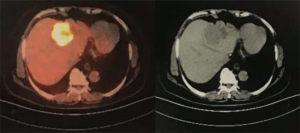

The patient agreed and signed informed consent for publication of her data. This study was carried out in accordance with the Institutional Ethics Committee of Shanghai Tenth People’s Hospital. A 70-year-old woman was transferred to Shanghai Tenth People’s Hospital complaining of right middle abdominal pain. A mass in the distal duodenum was identified after performing a gastroscopy. Pathological examination revealed poorly differentiated duodenal adenocarcinoma (Figure 1). Whole-body positron emission tomography-computed tomography (PET-CT) examination suggested multiple liver metastases (Figure S1), and the patient underwent transcatheter arterial chemoembolization (TACE) for the liver metastases. Therefore, the patient was diagnosed at stage IV. Genetic testing was performed in this patient to predict prognosis and guide clinical management. Next-generation sequencing (NGS) detected 35 gene mutations, small insertions/deletions or gene fusions related to targeted therapy or prognosis (Table S1). single-nucleotide polymorphisms (SNPs) of 13 genes associated with chemotherapy agents were also tested (Table 1). A gene test indicated that the patient was sensitive to oxaliplatin and fluorouracil. Based on the gene detection results and our experience, we treated her with palliative chemotherapy with two courses of XELOX (oxaliplatin 130 mg/m2 d1 + capecitabine 1 g/m2 d1–14 q3w). Tumor assessment by MRI showed stable disease. However, tumor markers (CA724: 42.86) were elevated. Therefore, using this information in conjunction with our experience in CRC, the patient was treated with XELOX plus bevacizumab (7.5 mg/kg) combination therapy. After 6 cycles of treatment, the patient disease status was stable with good tolerance of this regimen. Therefore, we continued this regimen as maintenance therapy with a longer treatment interval (every 4–6 weeks). Considering the neurotoxicity of oxaliplatin, stop and go policy was applied with oxaliplatin removed from cycle 16 to cycle 30 and added again in the next 10 cycles. After 20 courses of regimens (January 24, 2013 to June 18, 2014), the CA724 tumor marker decreased and was stable with continued treatment until disease progression (Figure 2). The treatment was well-tolerated with limited adverse effects. Totally, the patient underwent 40 cycles XELOX plus bevacizumab using stop and go policy for more than 3 years with stable disease from January 24, 2013 to November 24, 2016. The patient experienced Grade 3 proteinuria and Grade 2 neurotoxicity. An MRI scan on January 9, 2017 revealed disease progression of the liver lesions (Figure 3). Therefore, the patient received two courses of bevacizumab plus tegafur, gimeracil, and oteracil potassium capsules (50 mg BID d1–14) with irinotecan (180 mg/m2). She then underwent one course of high-intensity focused ultrasound (HIFU) therapy for the liver lesions. As shown in Table S1, no KRAS or BRAF mutations were detected, and therefore, the patient received targeted therapy with cetuximab (500 mg/m2 q3w) combined with irinotecan with a PFS of 10 months. However, the patient progressed again in January 2018. She was then treated with regorafenib, which is a third-line treatment option for patients with metastatic colorectal cancer. The patient died three months later because of a heart attack.